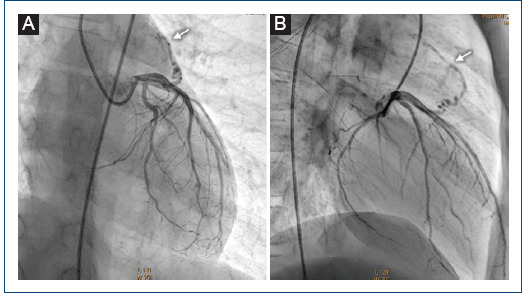

[Double coronary fistula: a rare finding in a pediatric patient].